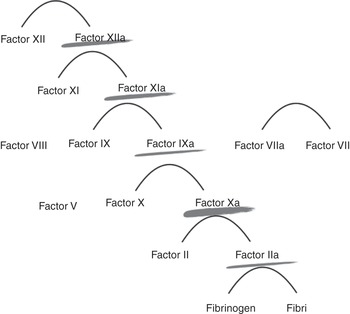

Heparin action is dependent on the presence of functional antithrombin in the patient and acts on the clotting factors IIa, Xa, IXa and XIa. The avidity to these factors will vary depending on the unfractionated heparin chain length and sulfation.

Heparin acts at various levels of the coagulation cascade, as shown in Figure 7.1.